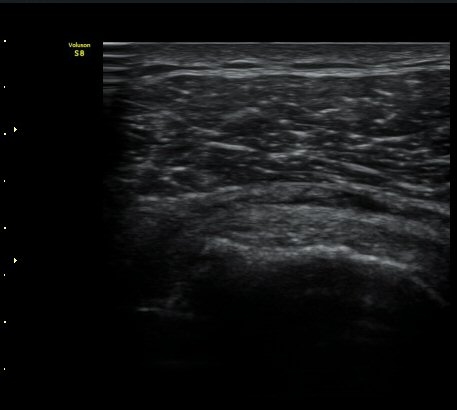

°ß°©ÇÏ±Ù°Ç ÁߺΠȾ´Ü¸é°Ë»ç»ó °ß°©Çã±Ù°ÇÀÌ ¾ã¾ÆÁö°í Á¡¾×³¶³» ¼ö¾×Àú·ù°¡ °üÂûµÊ

(±×¸² 8, 9).